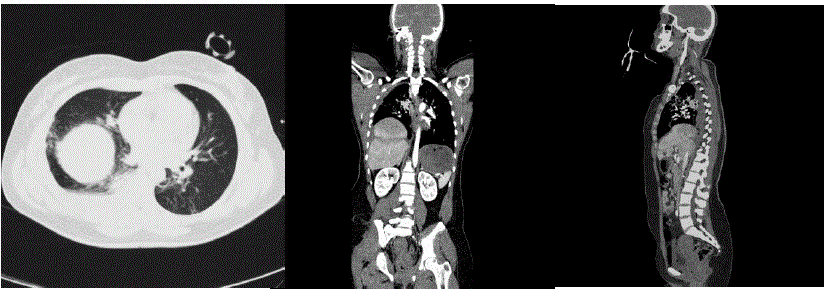

Realizada tomografia de abdome demonstrada a seguir: